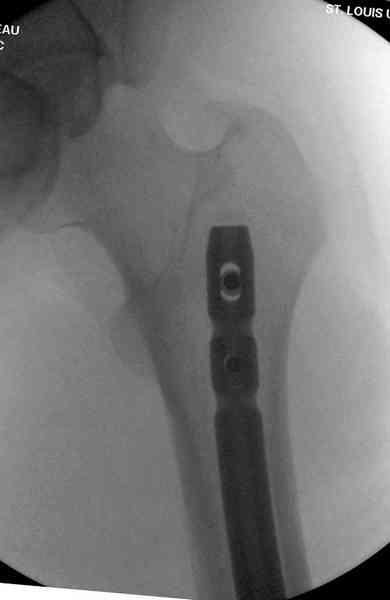

Пострадавшему 21 г., травма скоростная, после I&D с расширением раны, на бедре сделана операция ретроградным интрамедуллярным штифтом, остеосинтез с частичной резекцией надколенника и ушивание собственной связки.

На голень наружный фиксатор, рану на бедре ушили (рана была изнутри кнаружи всего 2 см). По протоколу травматических больных, до операции обследован ангиографически, (у больного дистально не смогли определить пульсацию) сосудистый хирург подтвердил проходимость на всем протяжении магистрального сосуда нижней конечности по снимкам ангиограмм.